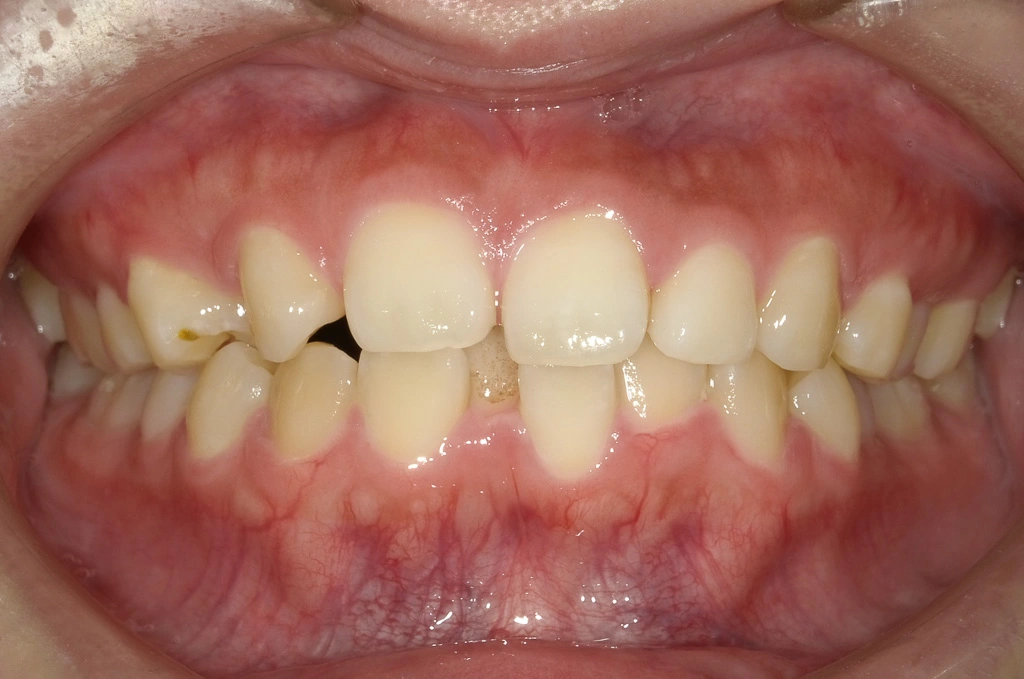

治療開始時

治療内容:第1小臼歯を3本抜歯し、ワイヤータイプの装置で矯正しました。